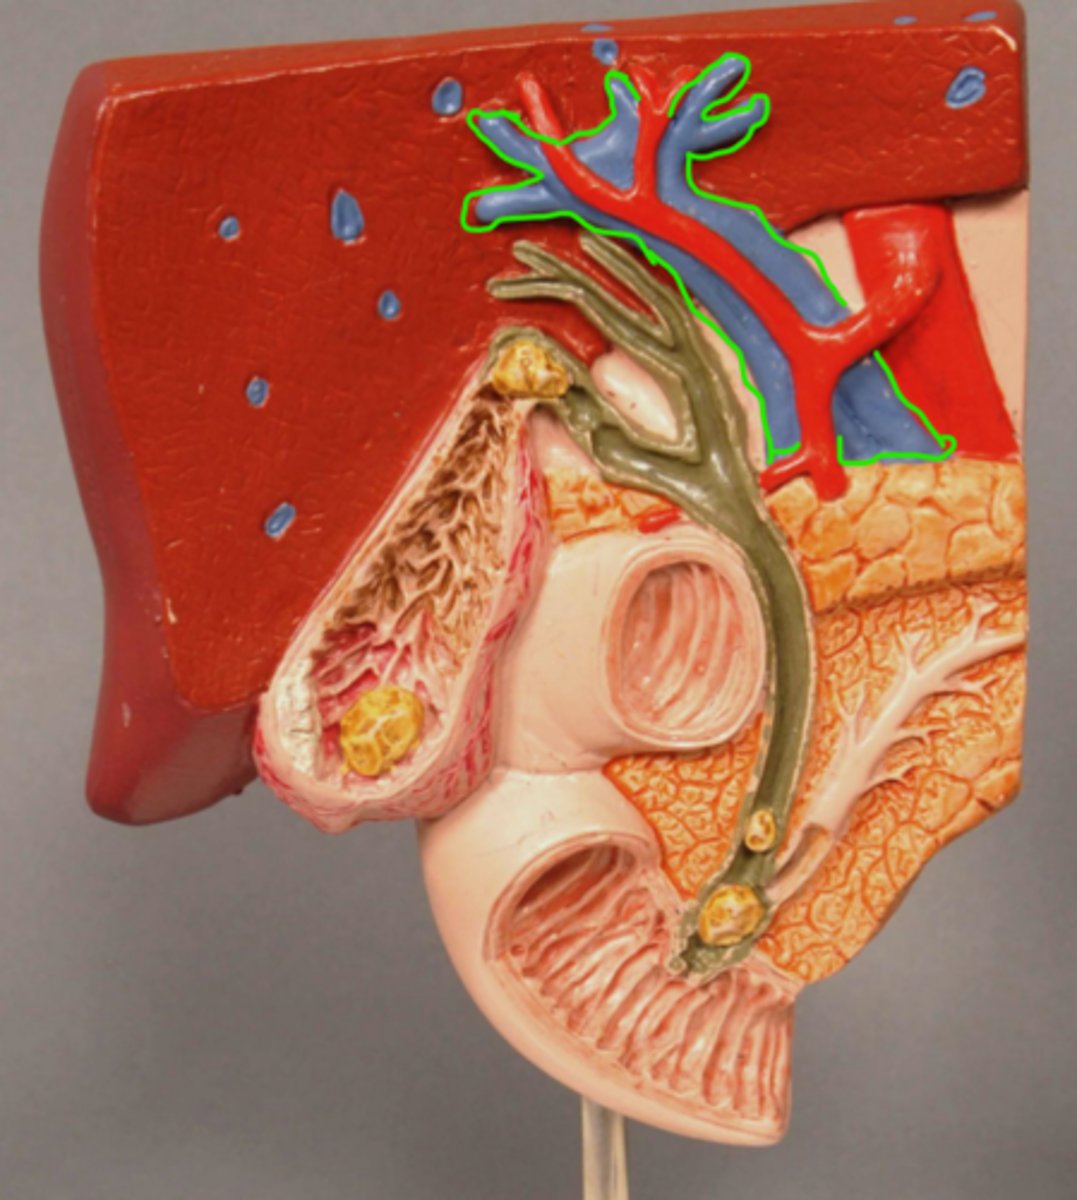

Left Hepatic Duct

Right Hepatic Duct

Common Hepatic Duct

Abdominal Aorta

Hepatic Portal Vein